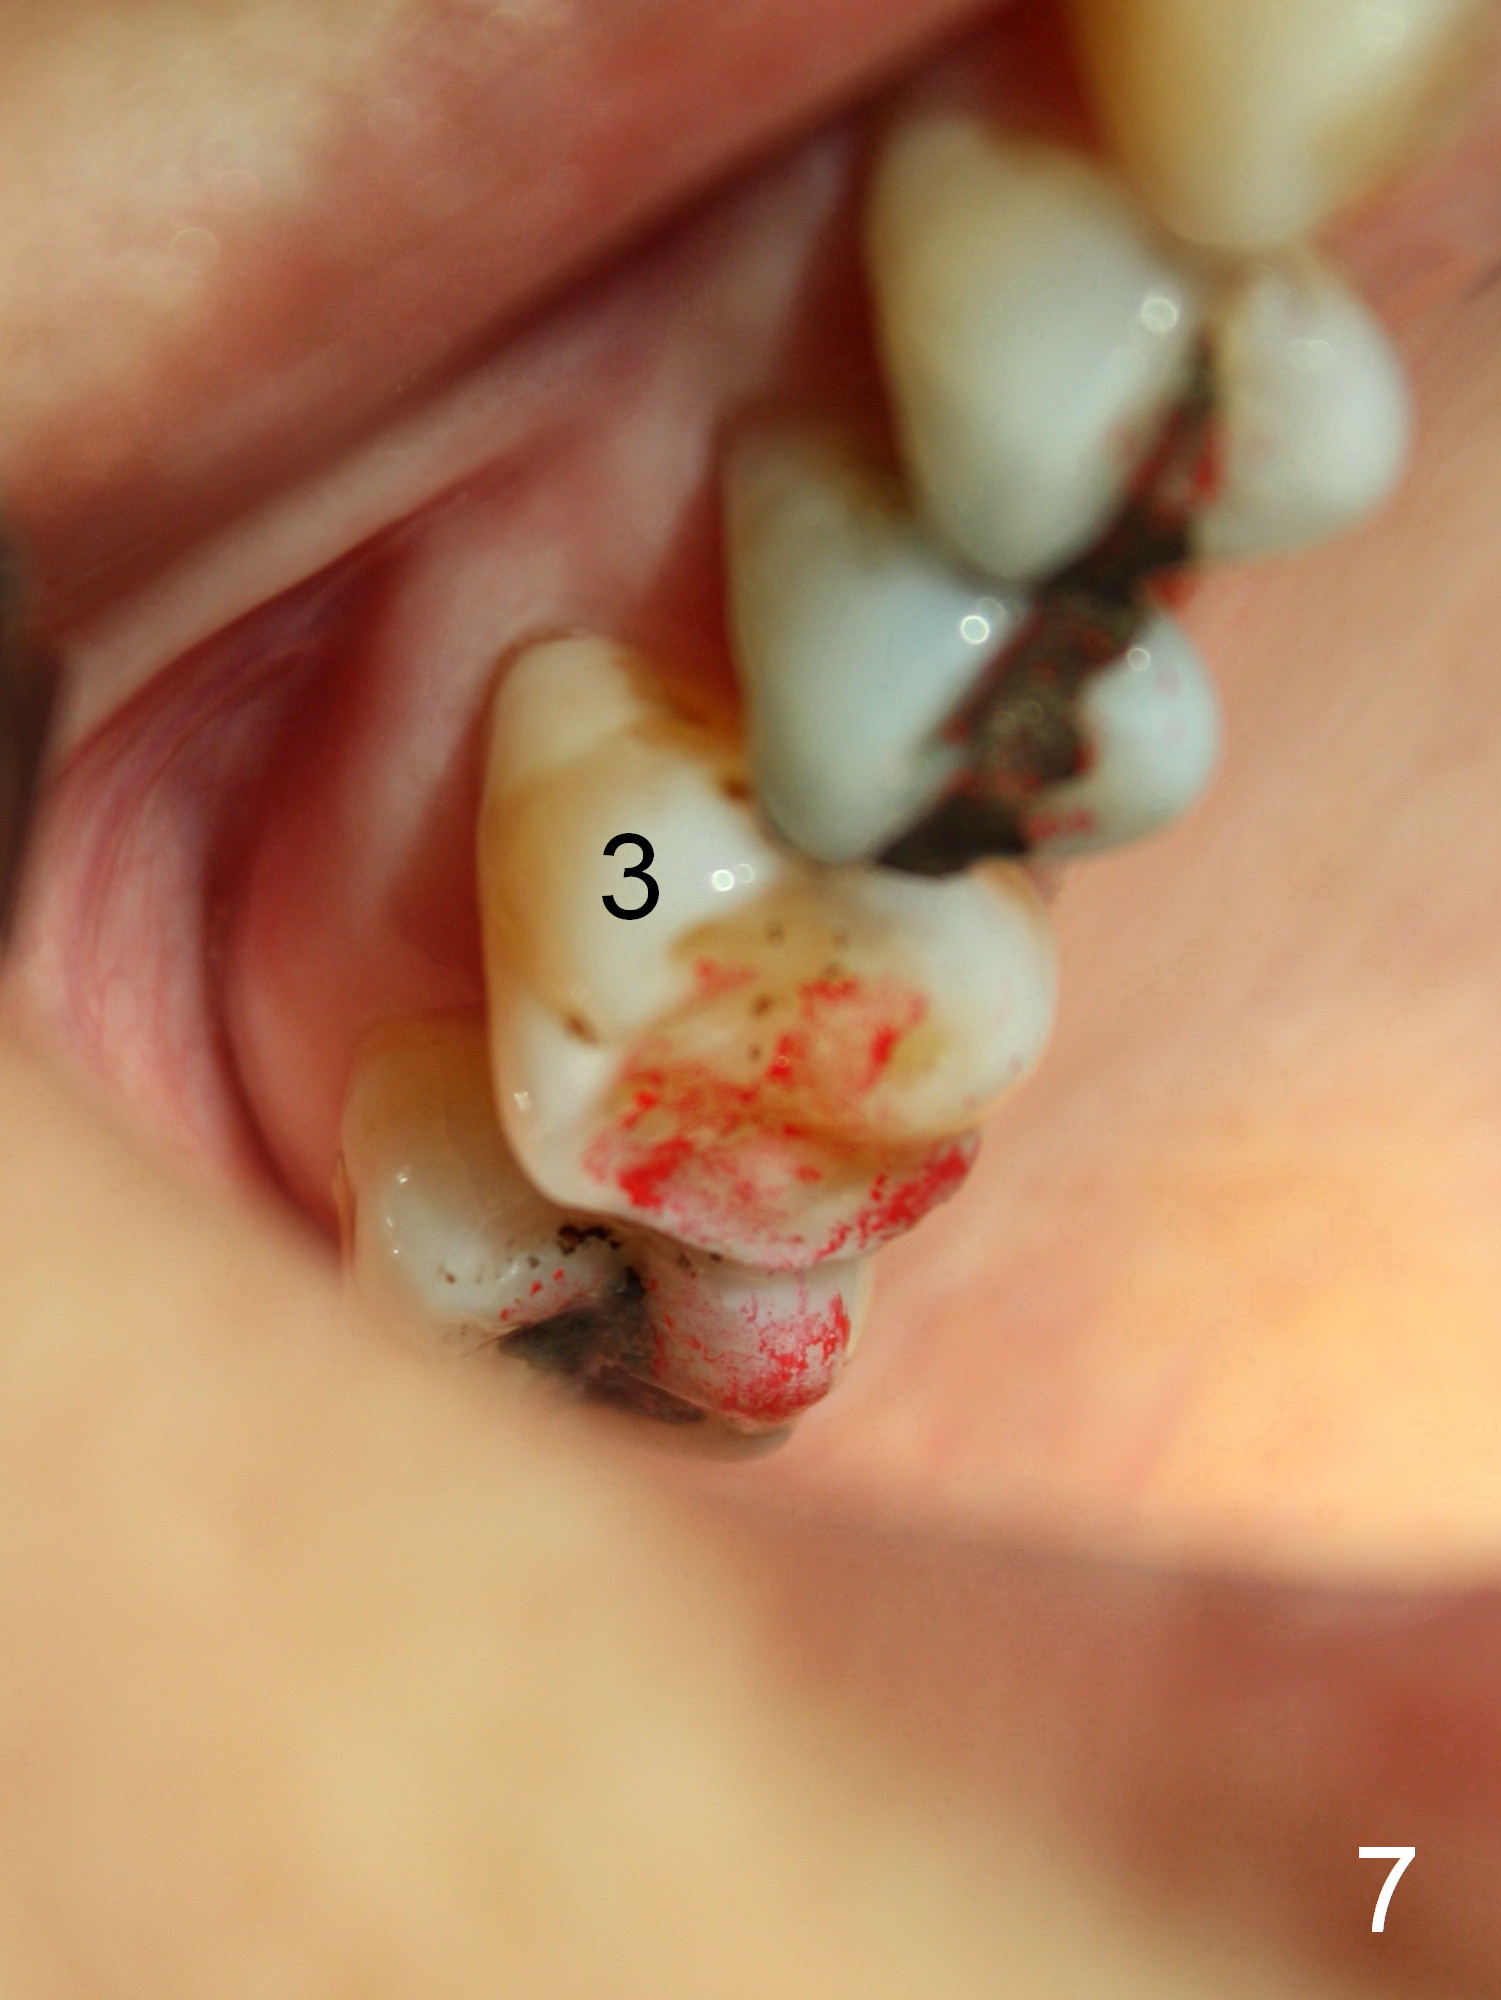

One year 2 months post cementation, the patient complains of inability to chew on the left. It appears that the crown at the site of #14 (Fig.8) is not as large as the tooth #3 (Fig.7); the occlusal contact of the crown is less than that of the tooth #3. The complaint remains the same after crown being remade. It appears that implant at #15 is needed (Fig.9: 1 year 9 months post cementation of #14 crown). The crestal cortical bone is thicker around the implant 2 years 4 months post cementation (Fig.10).